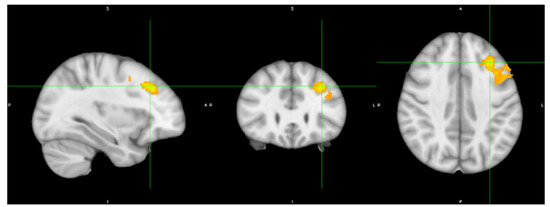

| Cluster Index | Brain Regions | Voxel | p-Value | Peak MNI Voxel | Z Stat-Max | ||

|---|---|---|---|---|---|---|---|

| x | y | z | |||||

| 1 | Middle Frontal Gyrus/Frontal Pole | 843 | 0.00184 | −32 | 28 | 38 | 3.81 |